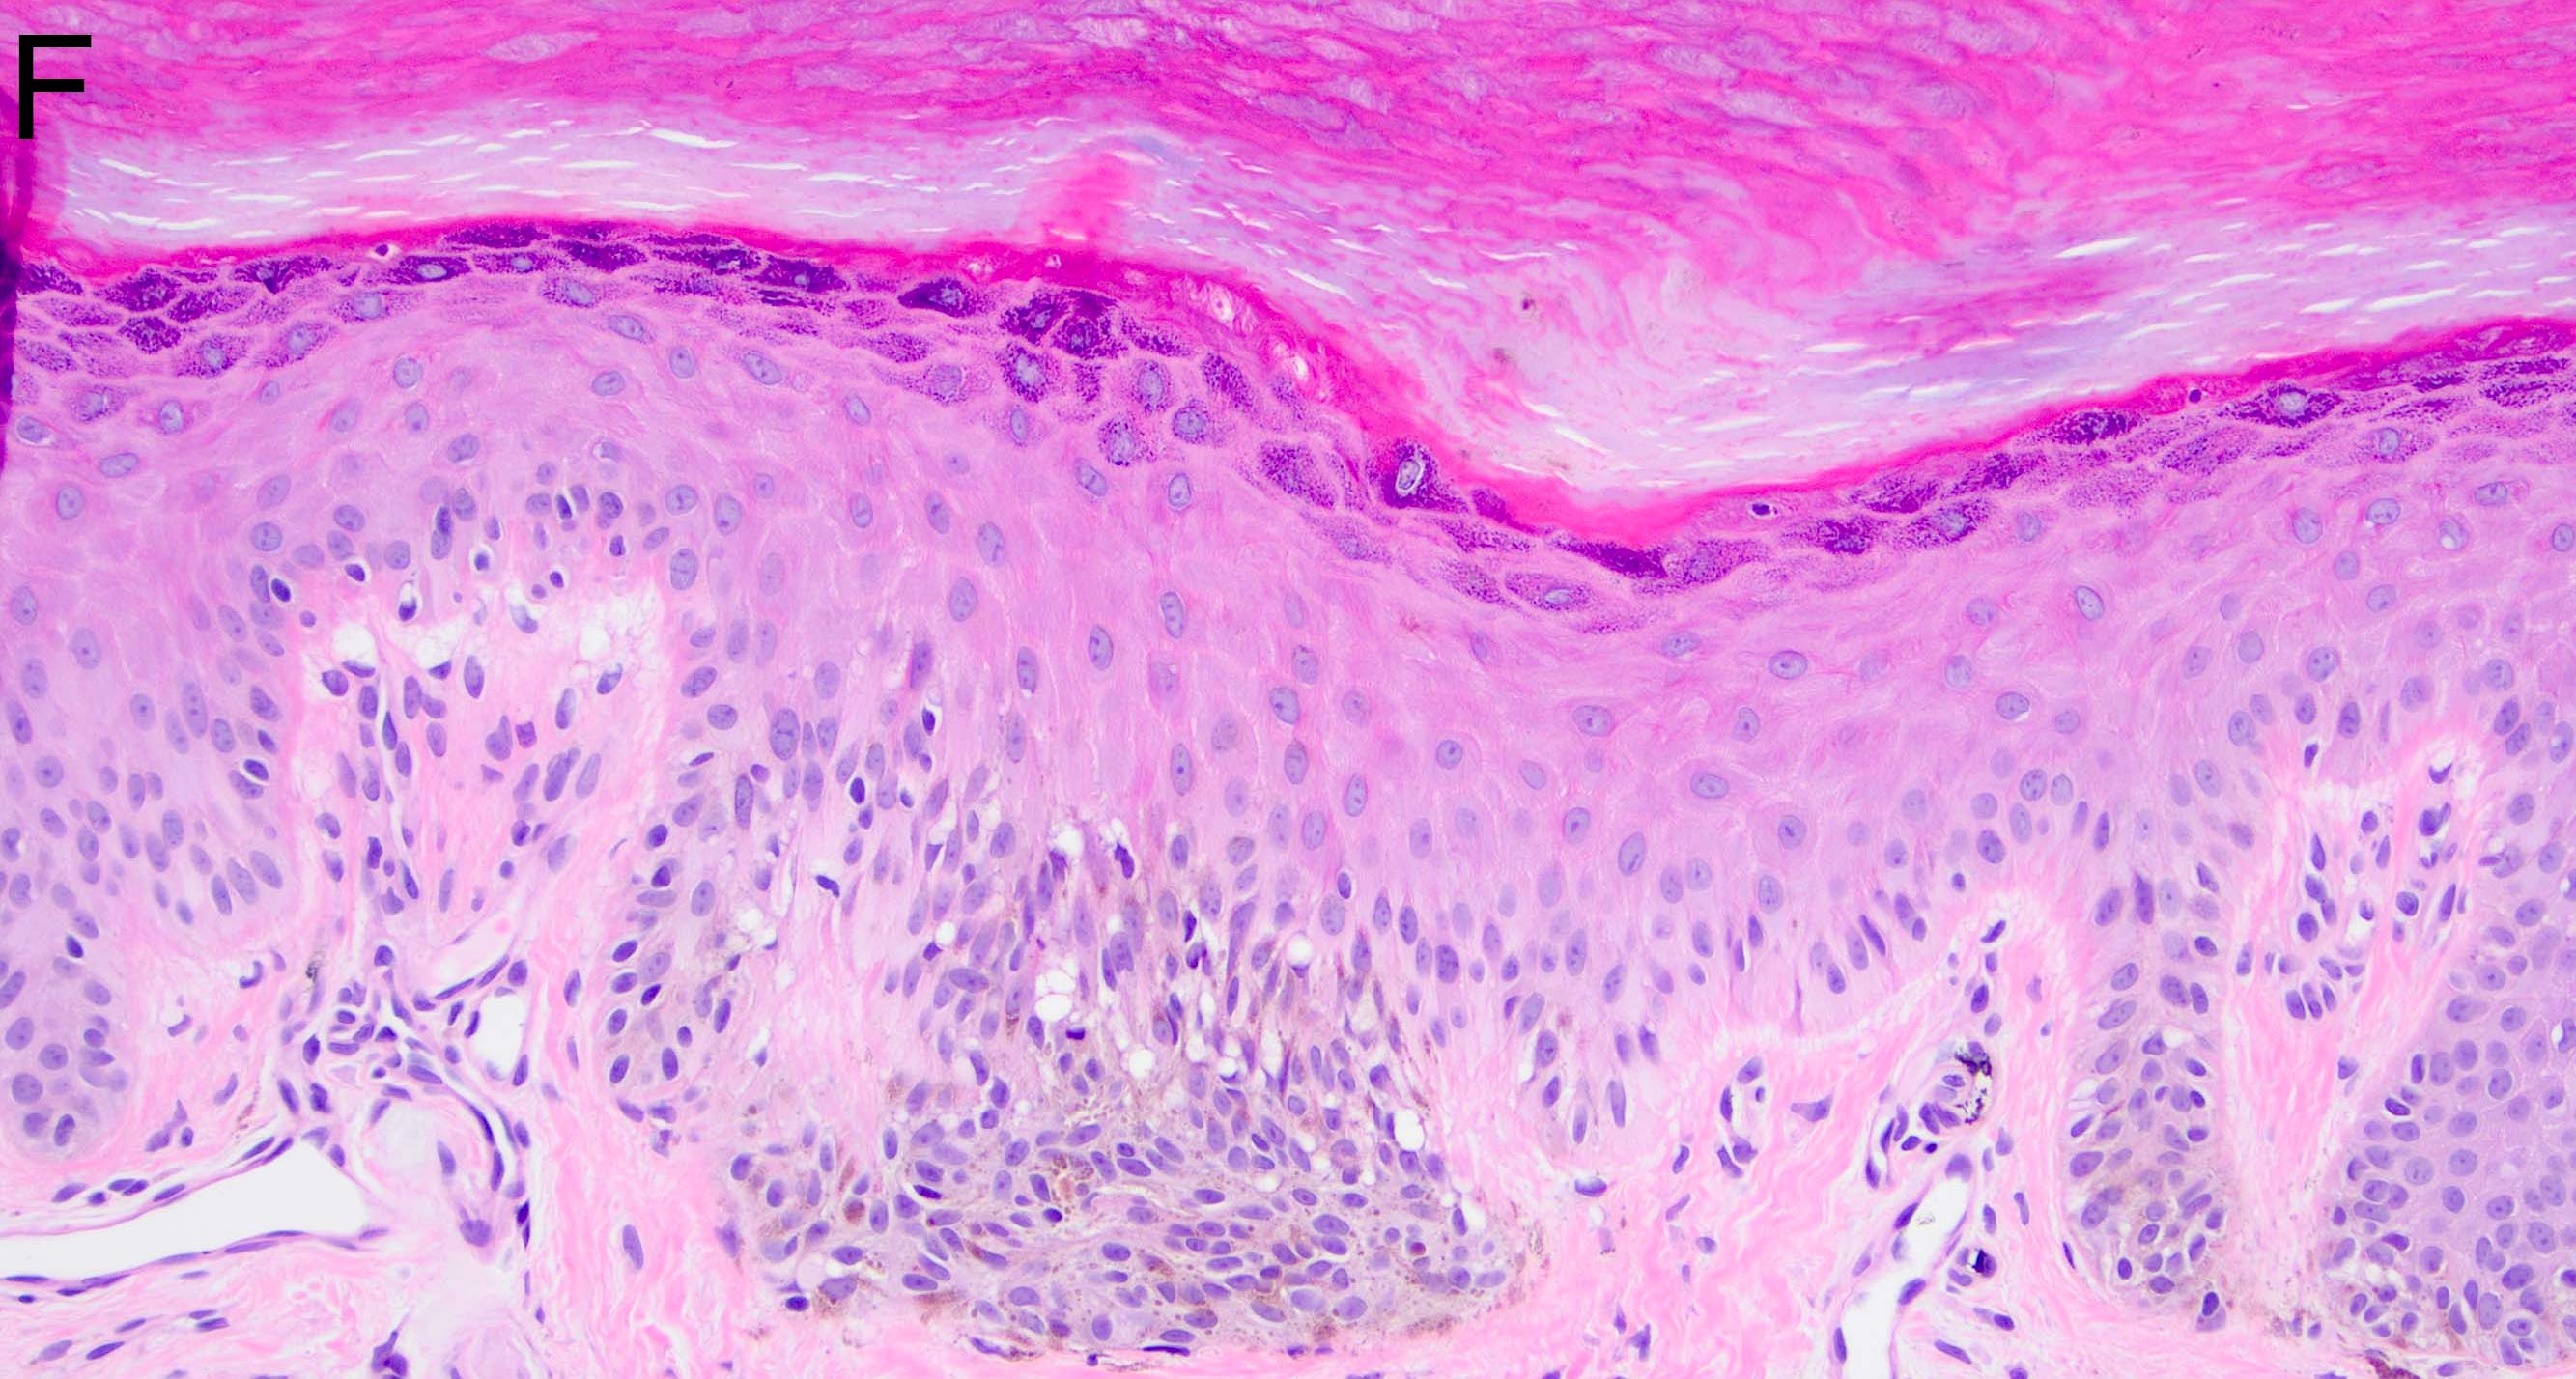

- Melanocytic nevi of the scalp (Am J Dermatopathol 2016;38:867):

- Melanocytes can be enlarged with irregular nuclei but atypia should be uniform throughout the nevus

- May contain large irregular nests in close proximity to one another

- Lentiginous growth may be prominent

- Pagetoid spread is a common feature

- Lesion can have broad junctional involvement and involve adnexa

- Single cell dispersion can be seen at lateral edges

- Lateral circumscription and maturation should be maintained, however symmetry may be lost (Am J Dermatopathol 2016;38:867)

- Prominent stromal fibrotic response can be seen